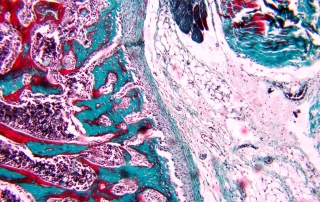

la première version de la formation en Histologie, Histochimie et Immunofluorescence organisée par l’AT-PNEI. Merci à tous les organisateurs, les formatrices et les participantes